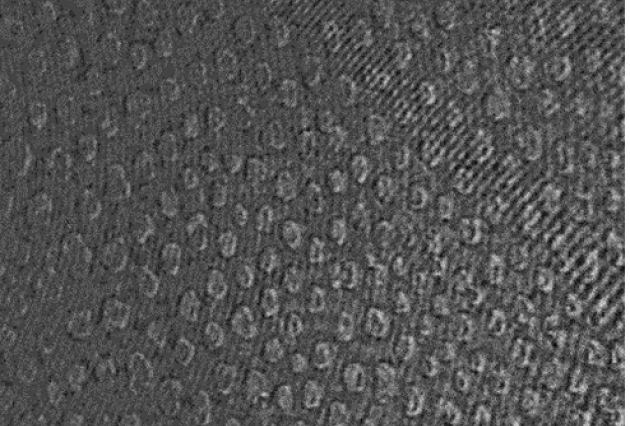

Publié le 03/08/2017Une membrane-modèle pour étudier l’effet de l’amoxicilline sur les cellules

L’amoxicilline (AMX) est un antibiotique dont le mécanisme d’action favorise la lyse et ainsi la mort de certains types de bactéries. L’AMX est le traitement classique pour lutter contre différentes (...)Lire la suite -

Publié le 03/08/2017Une membrane-modèle pour étudier l’effet de l’amoxicilline sur les cellules

L’amoxicilline (AMX) est un antibiotique dont le mécanisme d’action favorise la lyse et ainsi la mort de certains types de bactéries. L’AMX est le traitement classique pour lutter contre différentes (...)Lire la suite -